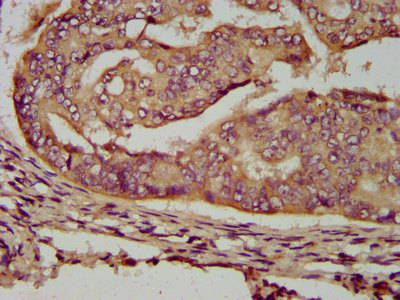

IHC image of PACO58204 diluted at 1:200 and staining in paraffin-embedded human endometrial cancer performed on a Leica BondTM system. After dewaxing and hydration, antigen retrieval was mediated by high pressure in a citrate buffer (pH 6.0). Section was blocked with 10% normal goat serum 30min at RT. Then primary antibody (1% BSA) was incubated at 4°C overnight. The primary is detected by a biotinylated secondary antibody and visualized using an HRP conjugated SP system.